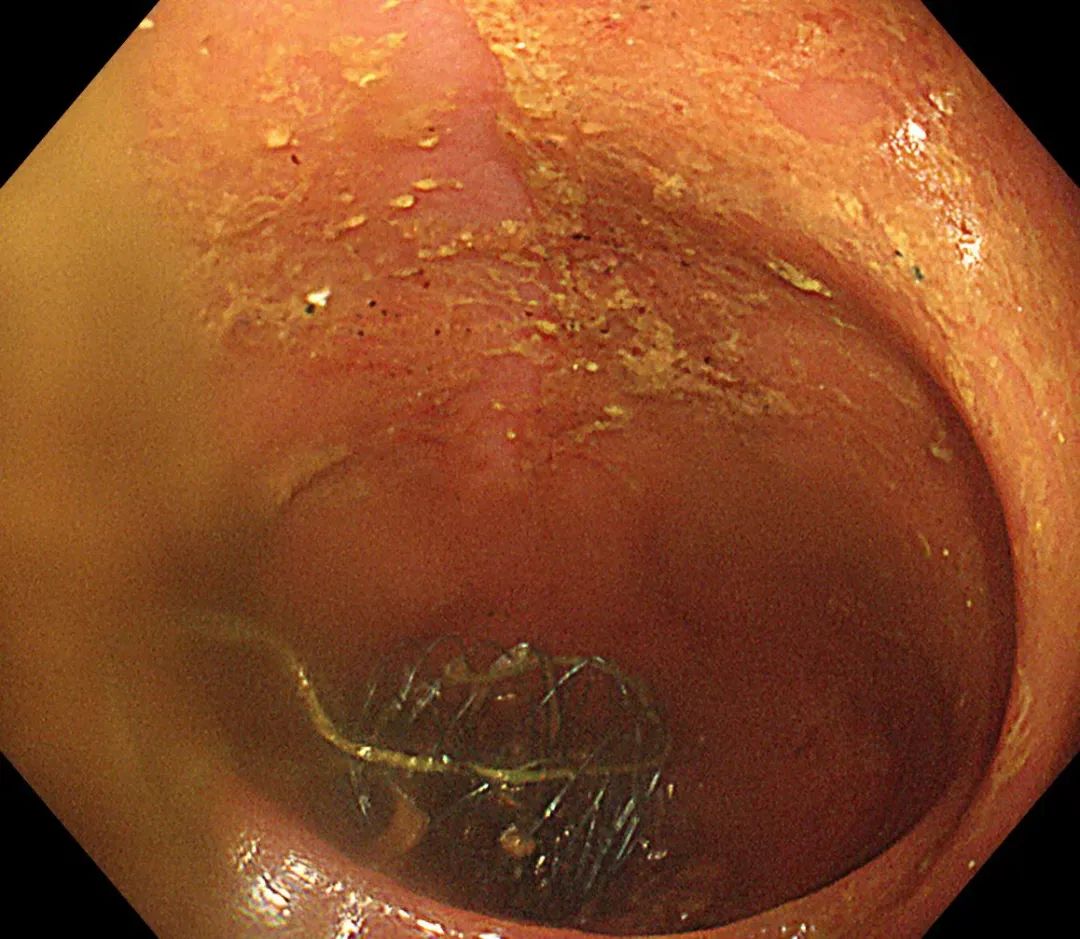

为快速缓解症状、解除患者疼痛,消化内科郭锐主任及张磊护师结合患者具体情况,决定给予肠道支架置入解除肠道梗阻,使患者免遭肠造瘘的痛苦,为择期手术切除直肠病变做好准备。由于病变导致肠腔严重狭窄,肠道支架置入难度也随之增加,郭锐主任凭借夯实的理论基础及高超的操作技术,通过 DSA 及肠镜联合引导,成功完成了肠道内金属支架置入术。术后患者能自主排便,腹痛、腹胀症状明显缓解,现已出院。

即在肠道狭窄的部位放置一个网状支架将肠道撑开,使狭窄或阻塞部位重新恢复通畅,可作为结直肠癌恶性梗阻的永久或暂时性治疗。肠道支架的过渡性放置,使梗阻性结直肠癌患者的肠道局部和全身状态恢复或接近无梗阻状态,2-3 周后再选择结直肠癌的 I 期手术方式处理,降低造瘘率、改善患者生存质量。肠道支架置入的引导方式有 DSA 引导和肠镜引导,DSA 引导通过注入对比剂能透视到狭窄近段肠腔扩张的程度,以及导丝是否确定在肠腔内;肠镜引导能直接清晰地看到狭窄远段肠腔的情况,尤其是狭窄段外口的具体位置;两者结合对重度狭窄、甚至闭塞的肠腔寻得一丝缝隙,使得支架置入获得成功。